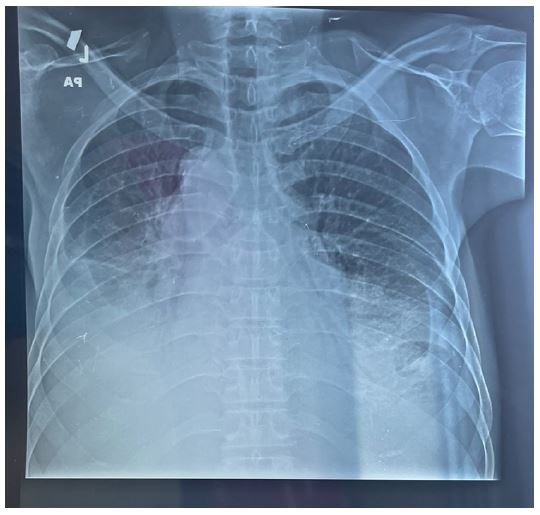

Presenting a 50-year-old immunosuppressed patient who was referred to our hospital for management of massive pre-tamponade pericardial effusion in respiratory distress. Patient was received in the emergency department and an emergency cardiac echography was done which confirmed the referral diagnosis of massive pre-tamponade pericardial effusion with massive bilateral pleural effusions. Patient was immediately prepared and taken for subxiphoid surgical drainage.

Patient was placed under general anesthesia, intubated and placed in the supine position on the surgical bed. Routing disinfection and surgical prepping was done. A subxiphoid median incision starting from xiphoid process to about 7 cm inferiorly was made. Subcutaneous and muscle fascia dissected and the xiphoid process amputated for better exposure of the pericardium. The bulging pericardium seen with a pericardiotomy made gently on the pericardium. Approximately 2 Liters of serohematic pericardial fluid was drained and a pericardial drain was placed in the pericardial space and connected to a self-expanding vacuum drain which was intended to drain the rest of the pericardial fluid. A biopsy of the pericardium was collected alongside 10cc of pericardial fluid and send for histo-cytology studies to determine the etiology of the effusion. Two thoracic drains were also placed and suture wounds closed up according to standard fashion and patient was taken to the surgical ward afterwards. Post operatively, cardiologist and infectious disease consults were requested for the patient. Post operative follow up was done. Histo-cytology results confirming TB as the etiology of the effusion. Patient was placed on anti TB medimedications by the infectious disease doctor and patient improved clinically and symptomatically with drained not producing anymore. Patient was later discharged 10 days post operatively and reviewed 2 weeks after with follow up cardiac echo and chest Xray not showing any pericardial effusion and pleural effusion respectively.